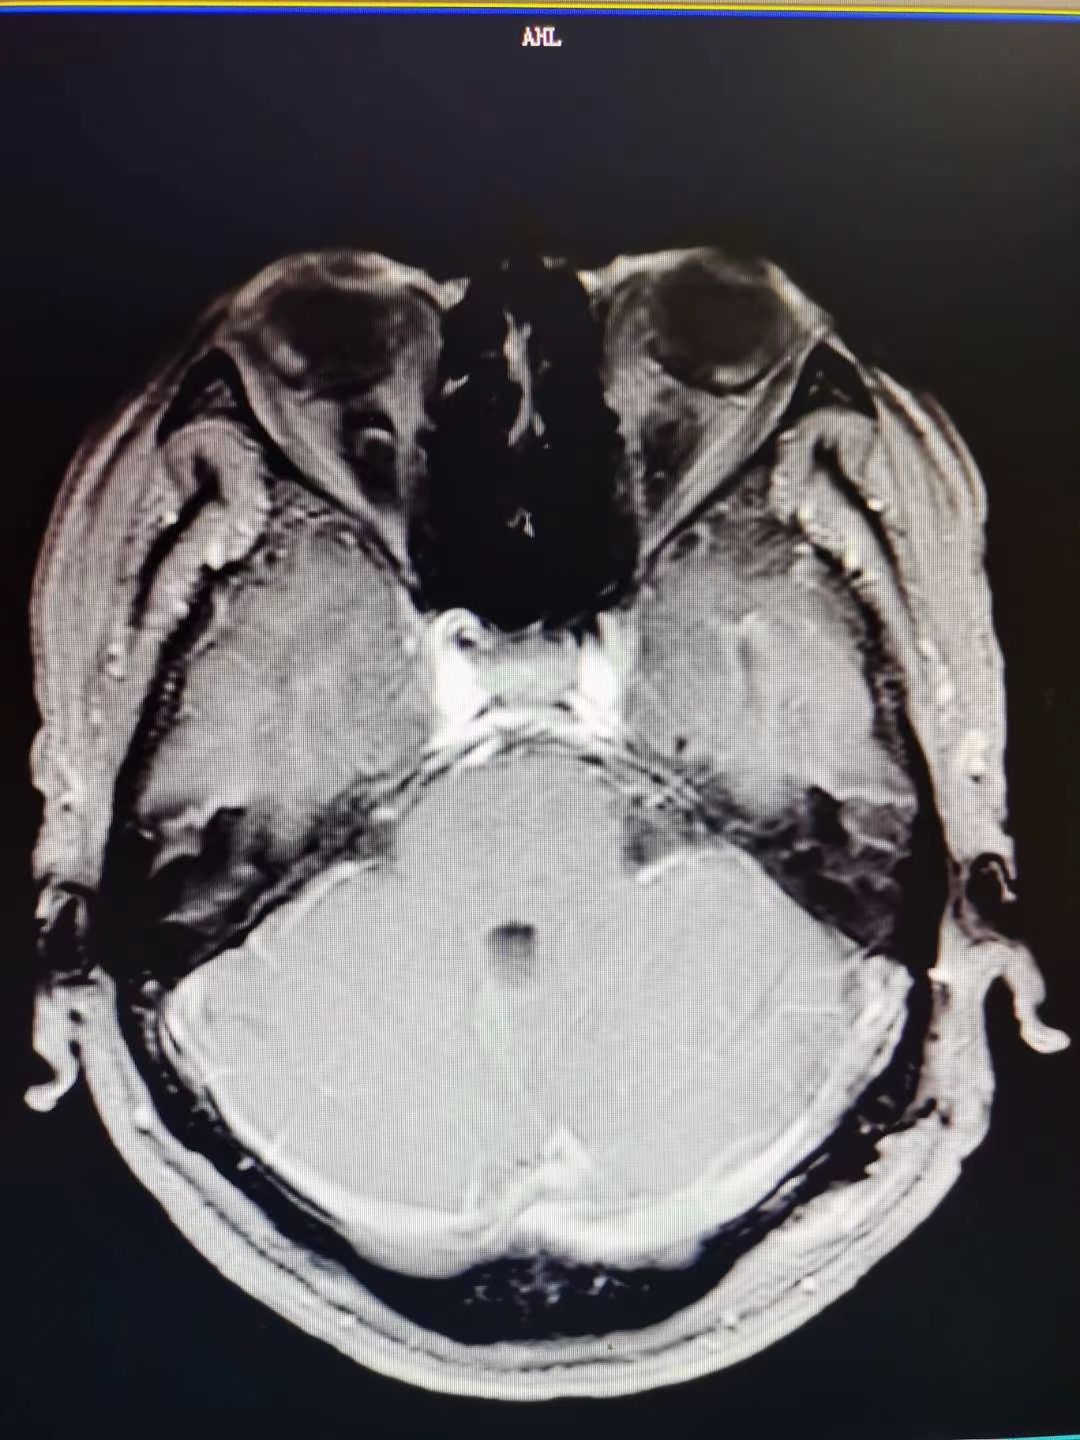

听神经瘤1例

肿瘤全切,术后面神经功能保留完好